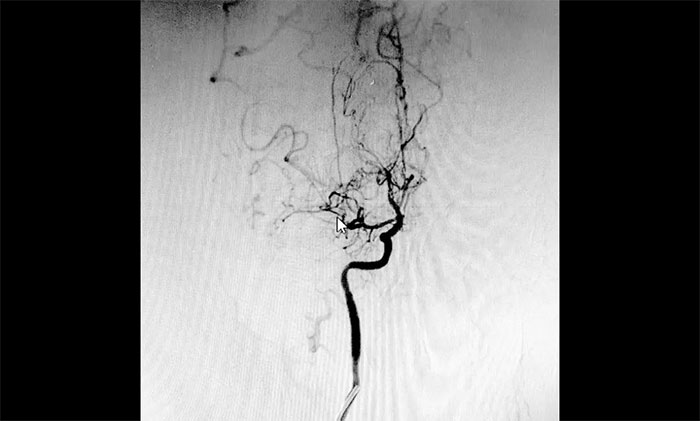

刚入院的范先生意识状态时好时坏,人非常消瘦,精神萎靡。神经外科于耀宇主任团队第一时间为其完善相关检查,DSA检查显示,患者双侧颈内动脉纤细,双侧大脑前、中动脉主干节段性狭窄,中远端分支明显减少,局部见代偿性异常血管网,符合烟雾病特征。

▲ 异常血管网形似“烟雾”

结合患者的影像检查报告,于耀宇主任团队针对病情和治疗方案展开审慎的讨论和评估,一致商定患者双侧大脑半球多发供血区灌注不足,左侧额叶部脑出血已过急性期,异常小血管仍可能反复破裂出血,应尽快通过血运重建手术,改善颅内血供、改善灌注、预防缺血性及出血性卒中二次发生的风险。